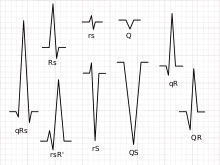

Any abnormality of conduction takes longer and causes "widened" QRS complexes. In bundle branch block, there can be an abnormal second upward deflection within the QRS complex. In this case, such a second upward deflection is referred to as R′ (pronounced "R prime"). This would be described as an RSR′ pattern.

Looking at the precordial leads, the R wave usually progresses from showing an rS-type complex in V1 with an increasing R and a decreasing S wave when moving toward the left side. There is usually a qR-type of complex in V5 and V6, with the R-wave amplitude usually taller in V5 than in V6. It is normal to have a narrow QS and rSr' patterns in V1, and this is also the case for qRs and R patterns in V5 and V6. The transition zone is where the QRS complex changes from predominantly negative to predominantly positive (R/S ratio becoming >1), and this usually occurs at V3 or V4. It is normal to have the transition zone at V2 (called "early transition") and at V5 (called "delayed transition").[11] In biomedical engineering, the maximum amplitude in the R wave is usually called "R peak amplitude", or just "R peak".[12][13] Accurate R peak detection is essential in signal processing equipment for heart rate measurement and it is the main feature used for arrhythmia detection.[14][15]

Terminology

Not every QRS complex contains a Q wave, an R wave, and an S wave. By convention, any combination of these waves can be referred to as a QRS complex. However, correct interpretation of difficult ECGs requires exact labeling of the various waves. Some authors use lowercase and capital letters, depending on the relative size of each wave. For example, an Rs complex would be positively deflected, while an rS complex would be negatively deflected. If both complexes were labeled RS, it would be impossible to appreciate this distinction without viewing the actual ECG.